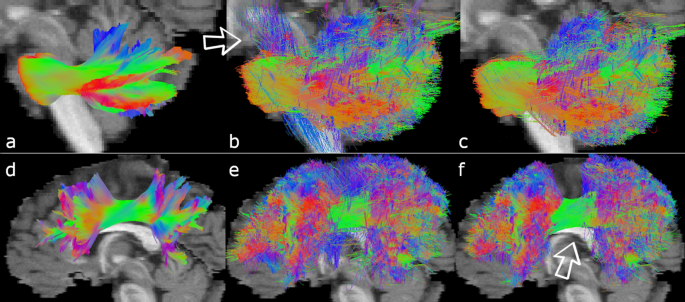

Recobundles led to poor results on some bundles. The top row shows the MCP in sagittal view. (a) 2015’s GT. (b) Streamlines recovered by Recobundles from all submissions. They include vertical streamlines that should not belong to the MCP. (c) Streamlines recovered using our new ROI-based segmentation. (d), (e), and (f) present similar patterns for the SLF.